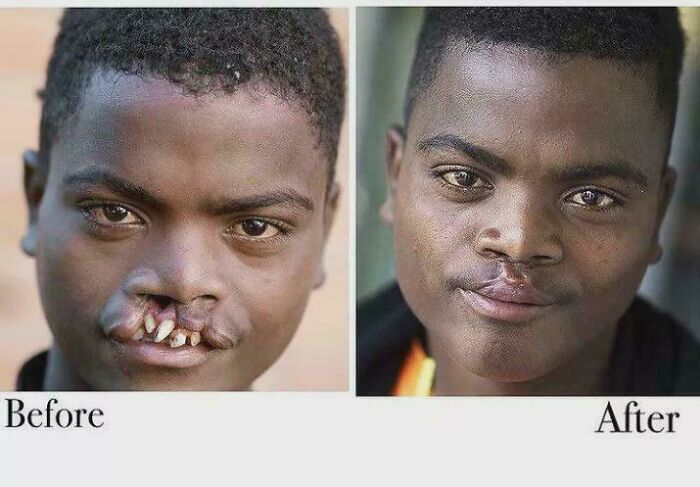

Craniofacial Duplication Surgery: Witness The Stunning Before & After